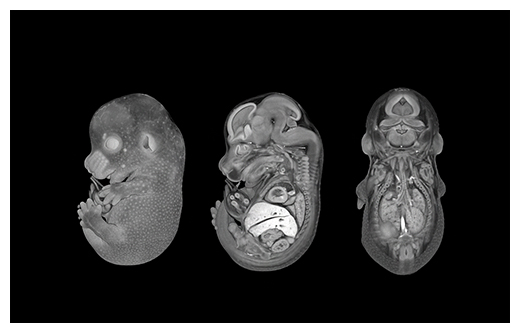

図2 新規解析法の一例:軟組織micro-CTイメージング法

従来の方法では困難であった軟組織の高解像度イメージングが可能。3D画像のため、サンプルを破壊することなく、さまざまな断面を詳細に観察できる。

田村 室長らは、X線CTを使って構成された画像の解析(図2)など、新たな解析技術の開発にも力を入れる。精神疾患に特化した表現型を調べる行動解析もその一つ。遺伝子を壊したマウスの行動を自動で追尾・機械学習する画像解析法(マーカーレスモーションキャプチャー)など、新しく開発した手法をIMPCに提案することもある。